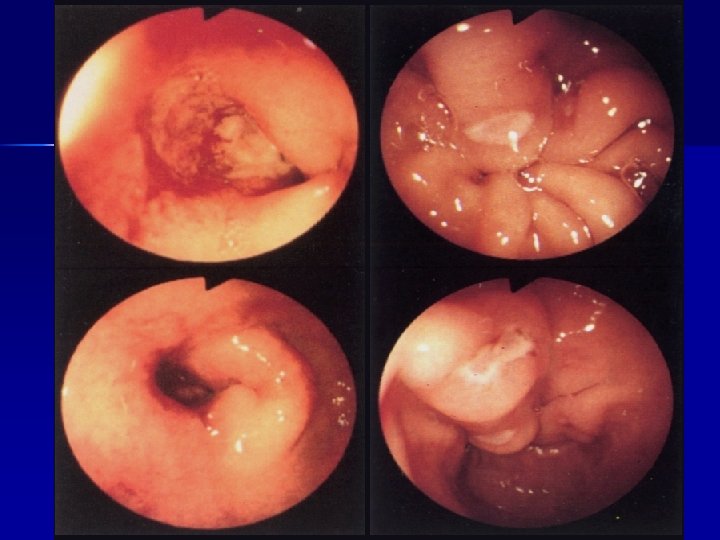

ENDOSCOPIA Lesioni del basso esofago n Patologia gastroduodenale(gastrite, ulcere, ernia iatale, corpi estranei) n Patologia rettocolica (colite ulcerosa, aspecifica, allergica, m. di Chronn) n